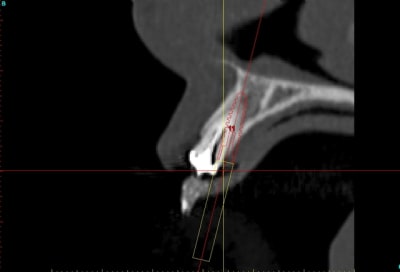

J'aurais bien aimé avoir des coupes radio avant/après.

C'est possible?

voilà, j'ai trouvé 5 mn...

le projet simplant est théorique, ça ne correspond pas à ce qui sera posé, c'était pour étude.